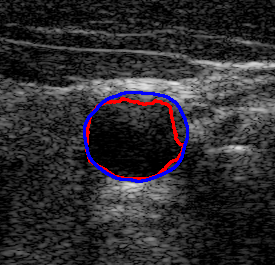

4.7 Downstream Task on Ultrasound Image Segmentation

To showcase the potential of the proposed denoising method quantitatively for ultrasound image understanding, we evaluate its impact on carotid ultrasound segmentation as a downstream task [9]. In this task, we use unseen noisy carotid images collected from the Clarius device. Then, unsupervised Segment Anything 2 (SAM2) [66] and the rule-based Flood Fill algorithm are used to extract the carotid artery from noisy and denoised images processed by various despeckling algorithms. In both cases, we place the seed point at the geometric center of the carotid lumen in each frame.

The quantitative result in terms of both IoU and AUC has been summarized in Table 6. To provide an intuitive visualization of the comparison, the results of SAM2 on a representative image and its denoised variants are presented in Fig. 12. It can be seen from Table 6 that the overall results using SAM2 are significantly improved in comparison to the Folld fill algorithm. This is primarily because of the strong generalization capability of the foundation model itself. Although the results produced by SAM2 across different images are comparable, the outcomes on images denoised by our method consistently demonstrate superior performance. The AUC reaches the highest score among all methods, while the IoU achieves the second-best performance. This performance advantage becomes more pronounced when using traditional region-growing algorithms such as the Flood Fill method. Significant improvements in both AUC ( vs ) and IoU ( vs ) are observed when applying the proposed Speckle2Self denoising approach.